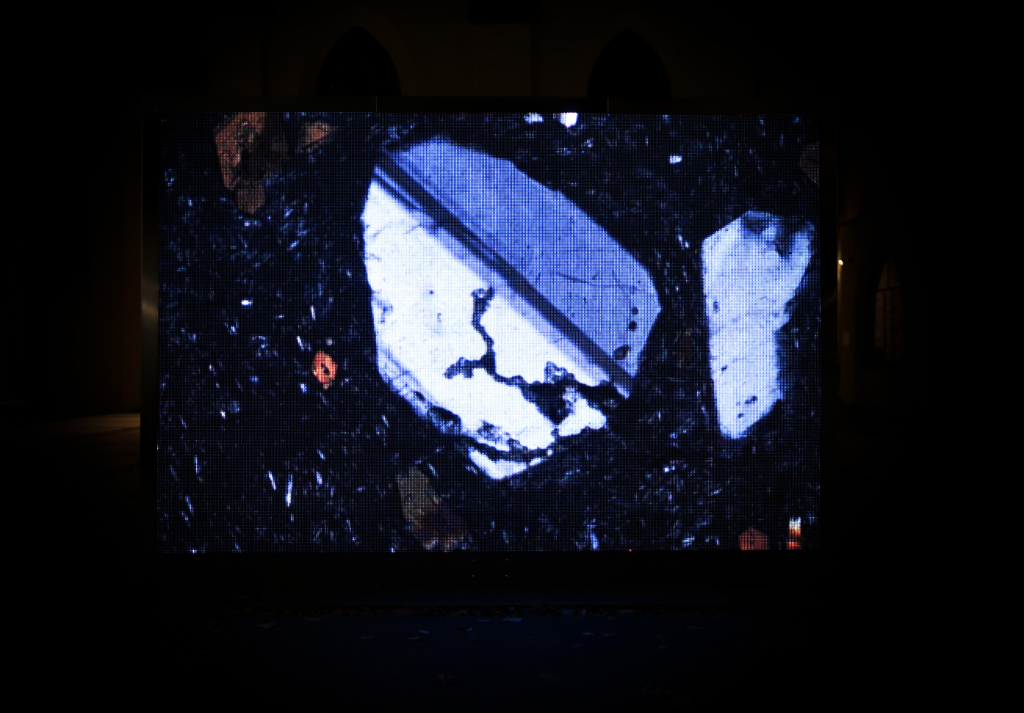

Once grown, the artist transplanted the explants into their corresponding transplanters. Inspired by organ manufacturing, these transplanters are 3D-printed kidney-shaped containers created through digital modelling based on the transplanted organ’s ultrasound and magnetic resonance images.

When I decided to start EXPLANTE, I was convinced that my kidney and I were in the right place to collaborate on this artistic level. Through this creative process, I got the opportunity to see and examine my kidney so close that I think I got to understand even better the whole process of having another organ as part of me.